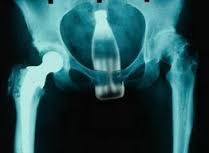

War beim Röntgen.

Hat recht, aber das falsche Bild übermittelt bekommen.

Will das richtige Bild unter Verschluss halten:

Verwechselt Bilder......

Hat sich im Tür geirrt, und war beim Tierarzt, der sich mit den Bildern vertan hat.